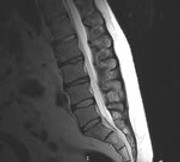

Was in der MRT Aufnahme Juli 2018 auffällig ist, sind die unterschiedlichen Höhen und die Farben der BS.

Je dunkler die BS, desto größer ist der festgestellte Wasserverlust der BS.

Diese Einbuchtungen an den Deckenplatten und hellen Stellen, sind aus meiner Sicht eher ein Hinweis auf Morbus Scheuerman.

Das ist eine Wachstumsstörung durch zu schnelles körperliches Wachstum in Kindheit und Jugend.

Die BWS zeigt auch schon schmale BS Fächer.

Was mir auch aufgefallen ist, dass die Aufnahme einen kl. Versatz von L5 zu S1 zeigt.

Zumindest steht L5 nicht mehr parallel zu S1 und kippt nach dorsal leicht ab

Das deutet auf Instabilität, bzw. Gleitwirbel hin und würde auch erklären, warum Stehen Beschwerden erzeugt.

Wurde schonmal gemacht. Die Bilder habe ich angefügt, ebenso ein upright MRT.

Bilder Funktionsröntgen: